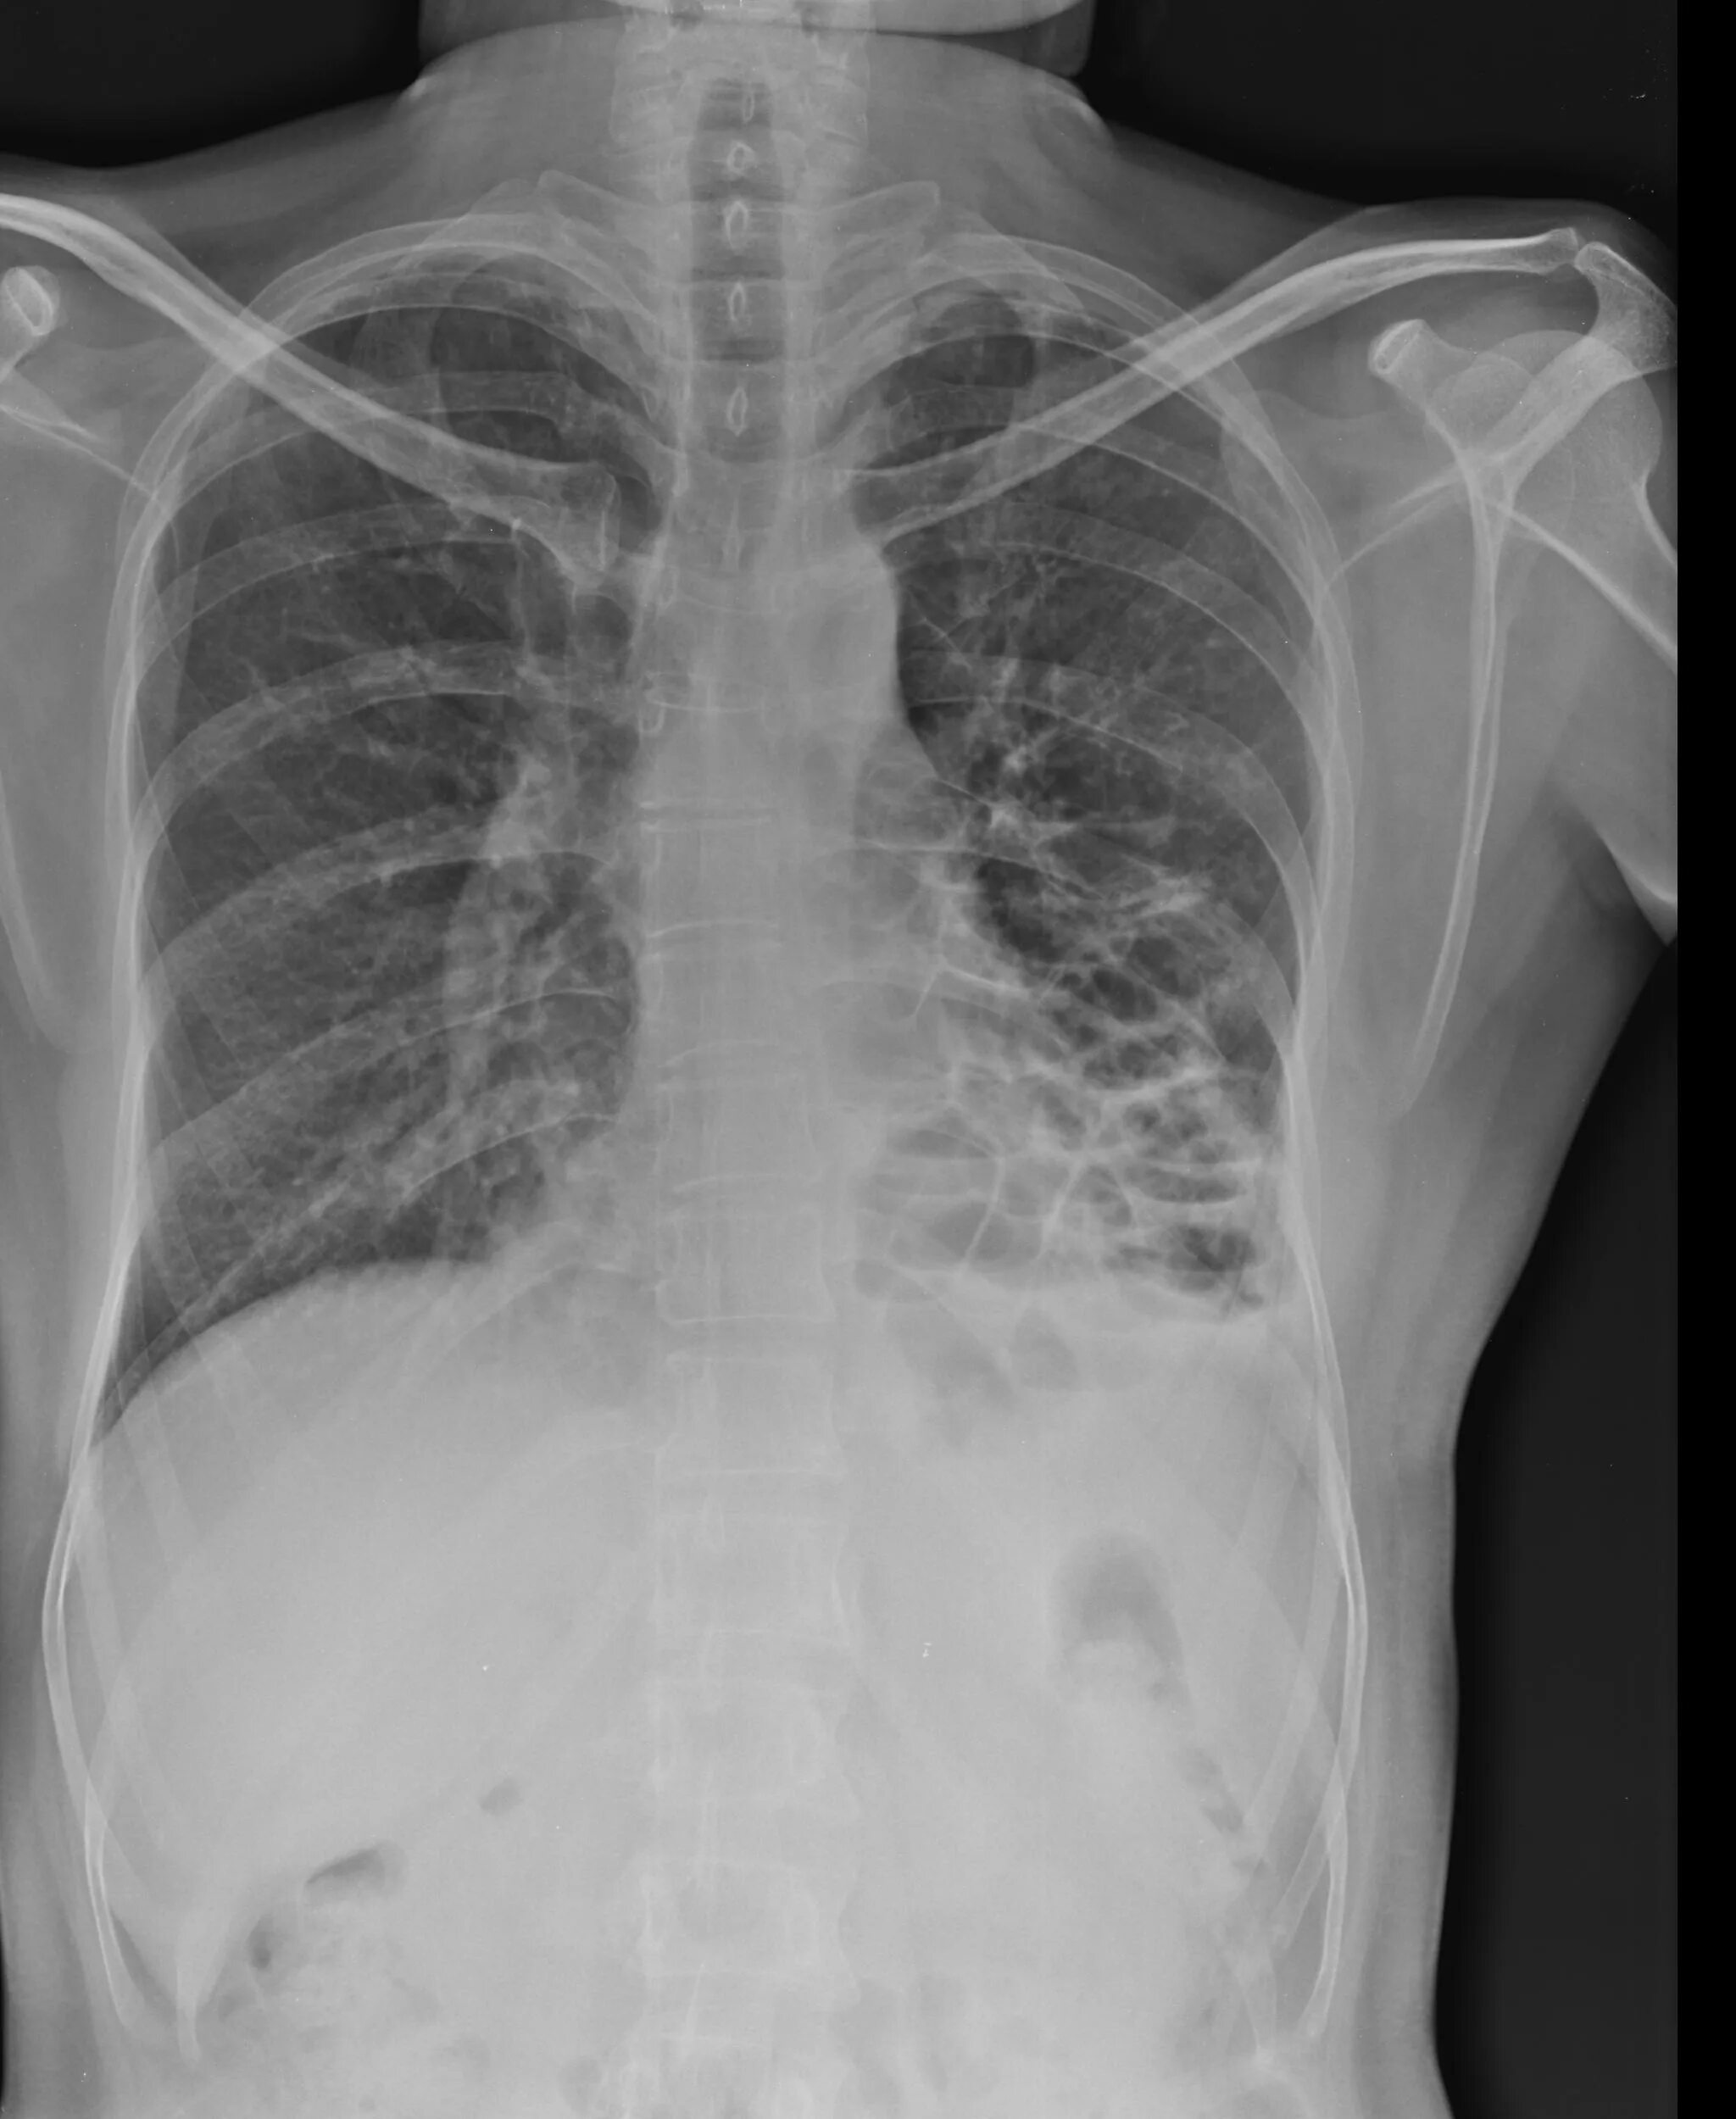

Source x rays